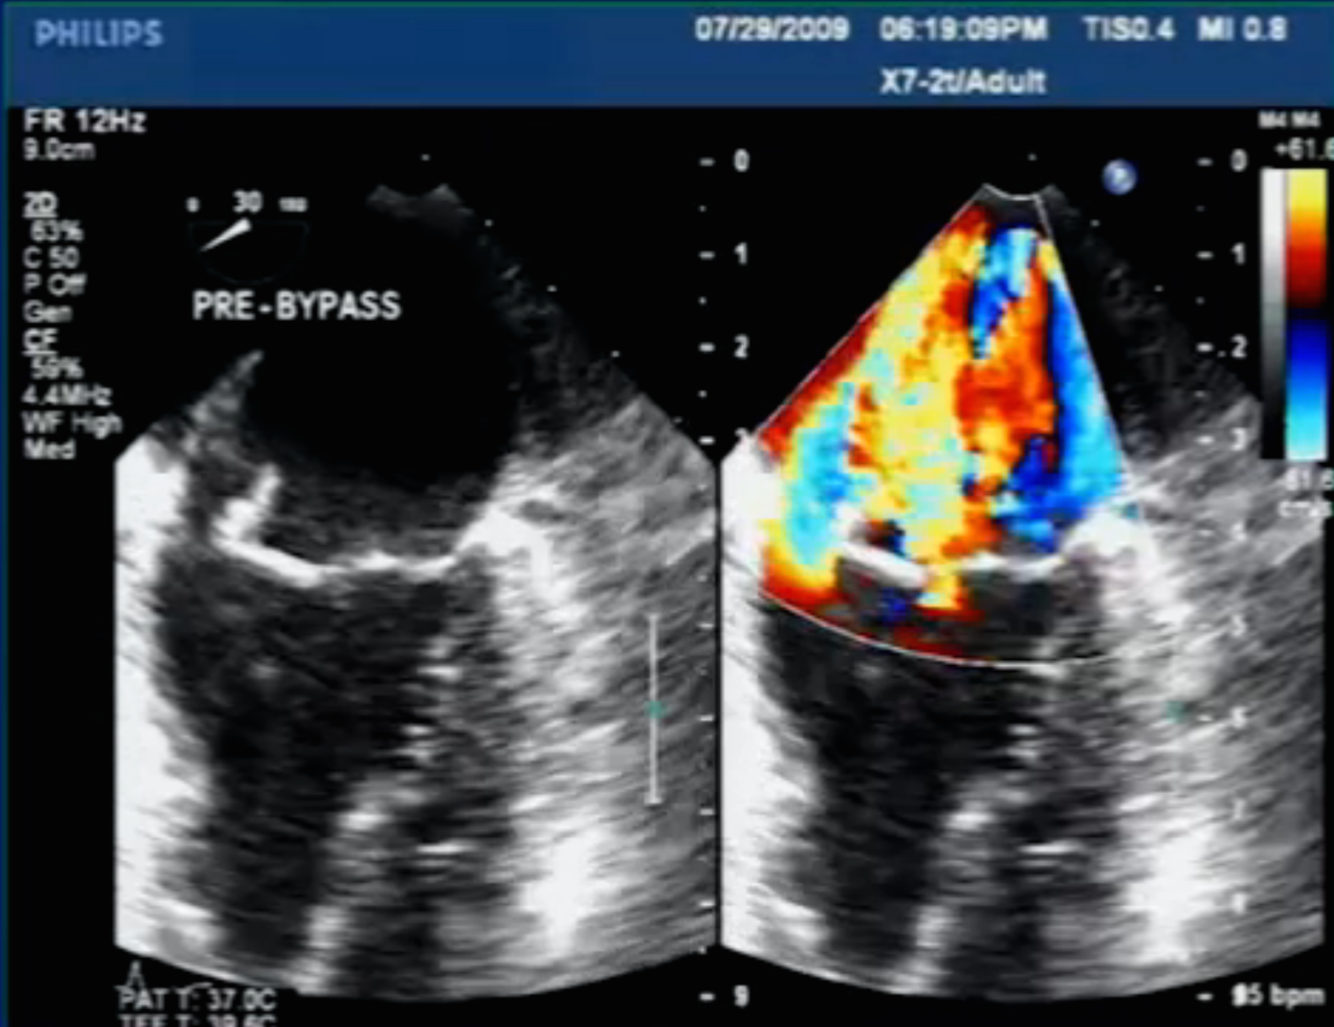

Diagnosis?

MAIF Phlegmon with Perivalvular Extension of Infection (PVEI)